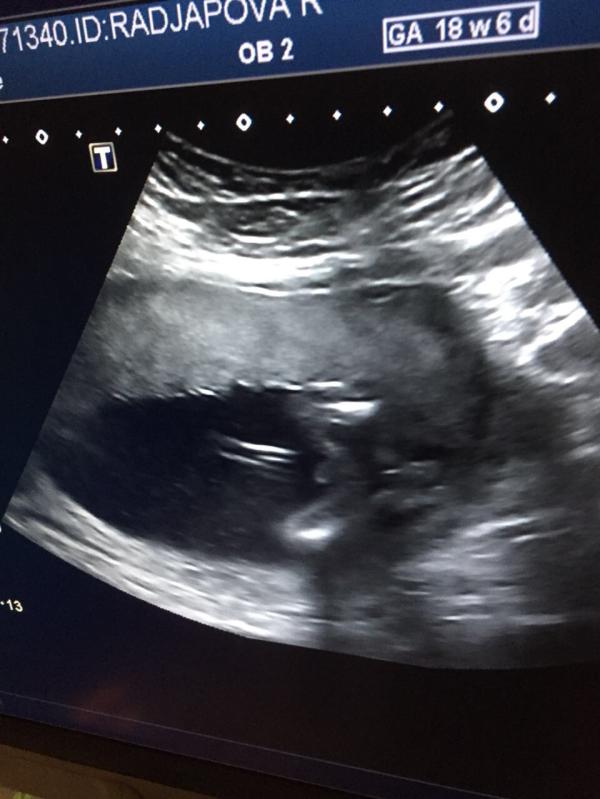

Прошли 2 скрининг) У нас будет мальчик) как назвать?)🤵💪